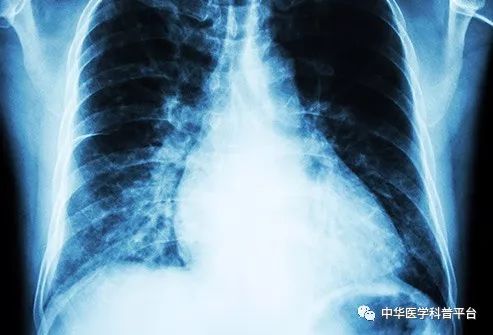

中风:高血压是中风的首要风险,中风一般分为两种类型:出血性和缺血性,出血性是指大脑中的动脉破裂,而缺血性是指斑块积聚或破裂,阻止了血液流向脑组织。如果你出现了脸部不对称,手臂无力或言语不利等症状,记得及时就医。